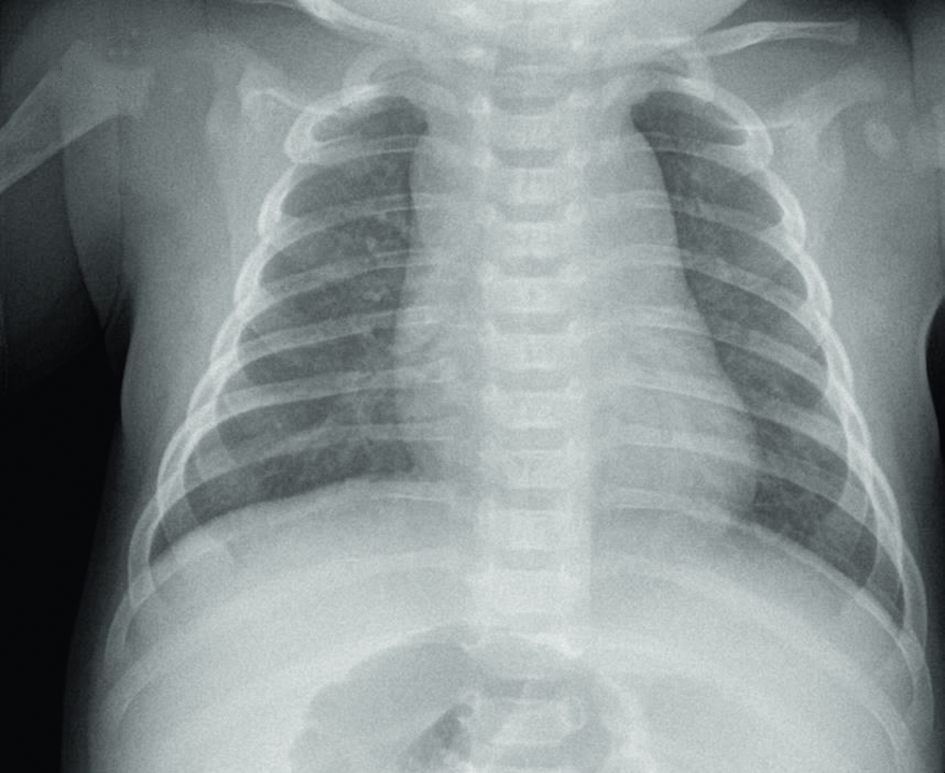

La radiographie thoracique (figure 126.1) montre typiquement une opacité de tonalité hydrique, initialement mal limitée puis systématisée (à un ou plusieurs segments, un lobe, un poumon), non rétractile, avec bronchogramme aérique pathognomonique mais inconstant (traduisant la persistance d’air dans les voies aériennes, figure 126.2), et une ligne bordante pleurale en cas d’épanchement associé. Si l’épanchement est abondant, l’aspect est celui d’un hémithorax opaque, sans bronchogramme aérique, refoulant le médiastin du côté opposé à l’épanchement.

Fig. 126.1 Radiographie thoracique normale de face d’un nourrisson de 2 mois : thymus normal.